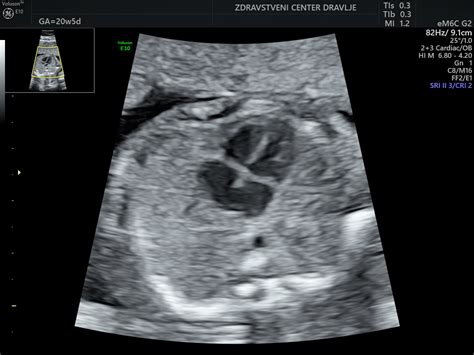

Če se ostanek nosečnosti iz maternice izloči v celoti sam od sebe, govorimo o popolnem spontanem splavu. Včasih pa se nosečnost ne izloči v celoti. Ginekolog pri pregledu ugotovi, da plodu srce ne bije več. Takšni obliki izgube nosečnosti pravimo zadržani splav. V nekaj odstotkih nosečnosti ginekolog ob prvem pregledu med šestim in devetim tednom po zadnji menstruaciji ugotovi, da je v maternici le prazna gestacijska vrečka brez ploda.

Simptomi molarne nosečnosti so lahko podobni kot pri spontanem splavu: krvavitev iz nožnice, povečana maternica zaradi razraščanja posteljice, prekomerno bruhanje zaradi močno povišanega nosečnostnega hormona in napetost v trebuhu. Diagnozo postavimo s pomočjo ultrazvoka, ko v maternici vidimo mehurčasto strukturo brez ustrezno velikega ploda, ter na podlagi povečane koncentracije nosečnostnega hormona v krvi. Zdravljenje je kirurško in poteka z zdravili, dokler nosečnostni hormon ne izgine iz krvi.